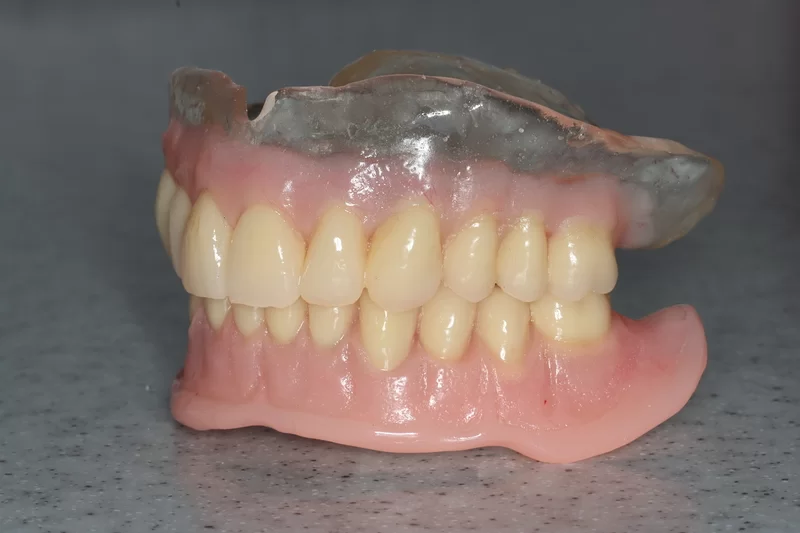

Case 37 – Implants

Upper complete denture and lower implant retained complete denture